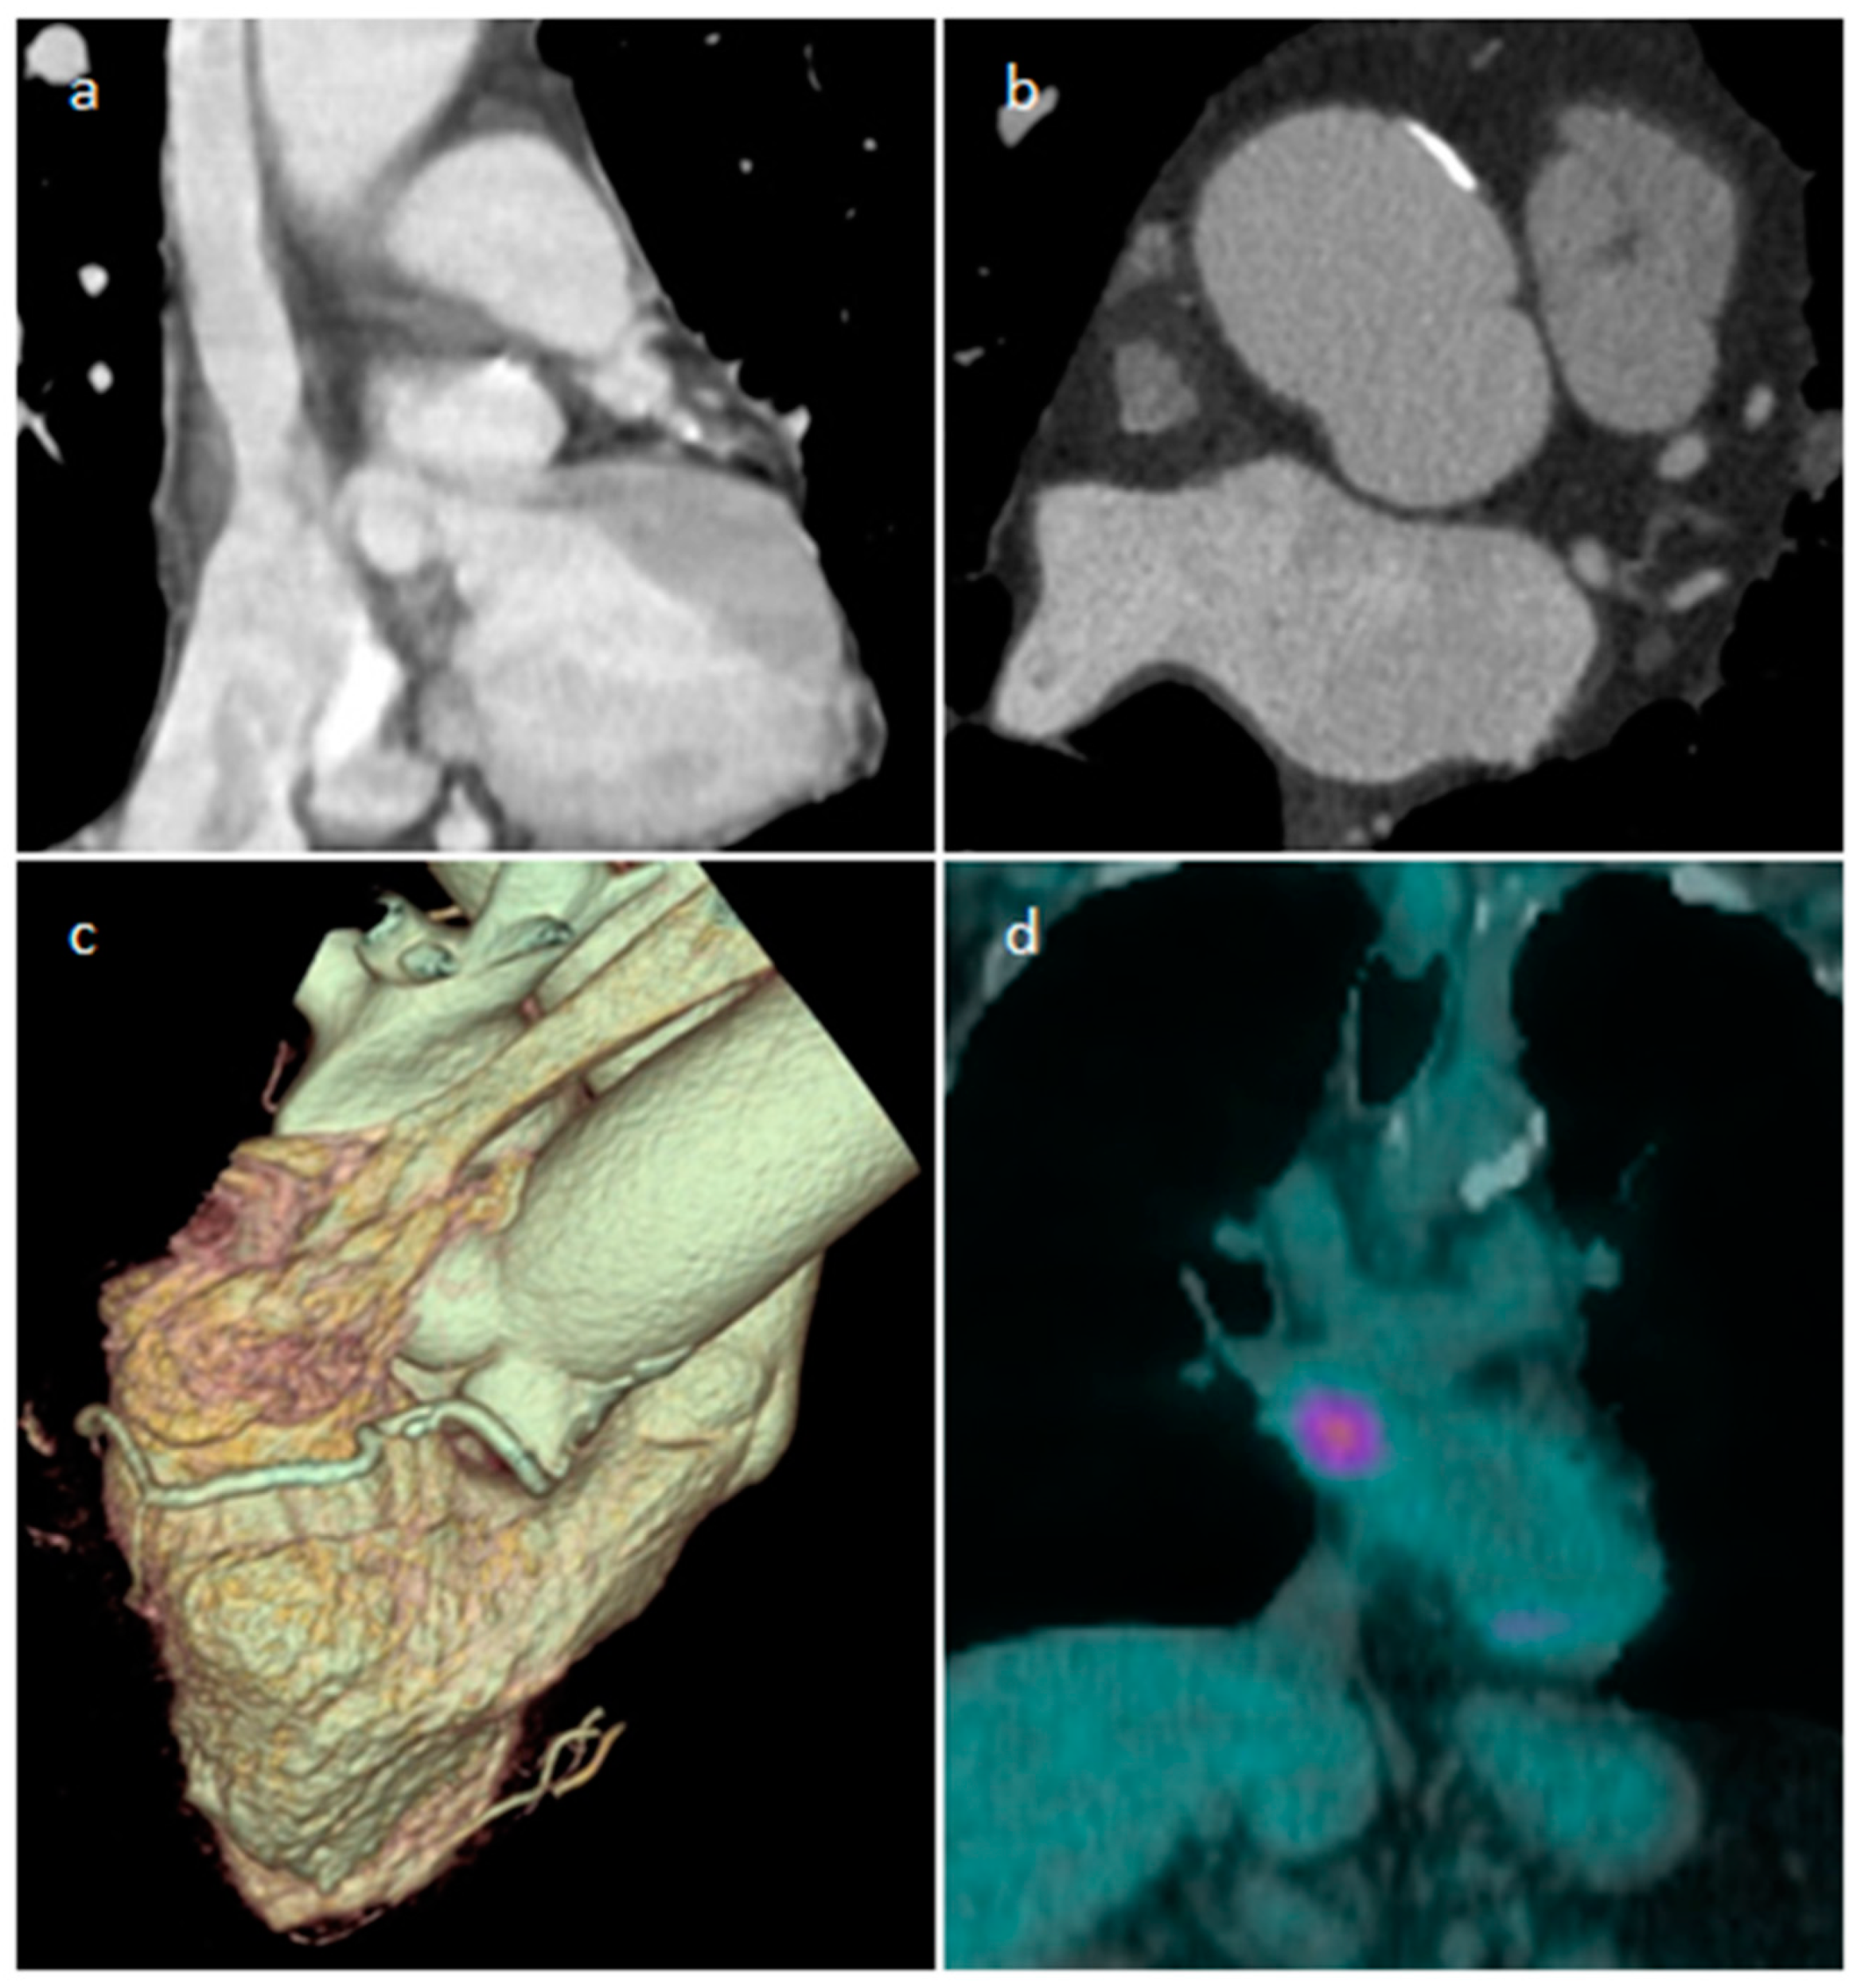

2.2. Lipomatous Hypertrophy of the Inter-Atrial Septum (LHIS or LHAS)

| LHIS | Late adulthood. Obesity | IAS | Usually, asymptomatic. Atrial arrhythmias | mass like deposition of brown fat in the IAS which spares the fossa ovalis | Homogeneous hyperechoic dumbbell appearance of atrial septum | mass with fat-attenuation which spares the fossa ovalis | Hyper T1w and T2w, no LGE, hypo on STIR and other fat-suppression sequences |